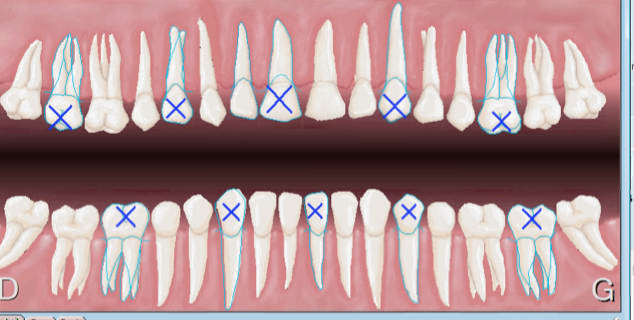

Ici radiographies de 4 secteurs centrés sur 25 26 35 36. -)

Et ca tu cotes comment ? -)

(18, 17, 16) (15, 14, 13) ( 12, 11, 21) (22, 23,24) ( 25,26,27)

Vous n'optimisez pas vos clichés mon cher. Mes secteurs de 3 dents contigus sont bien DISTINCTS pas les vôtres. -)

Ecart de 2 dents aussi 16 et 15 par exemple pour des radios centrées sur 17 et 14 . Mouhahaha !

le dénombrement max c'est

18 16 14 12 21 23 25 27

en bas pareil

et la CCAM n'a pas de code pour 16 secteurs